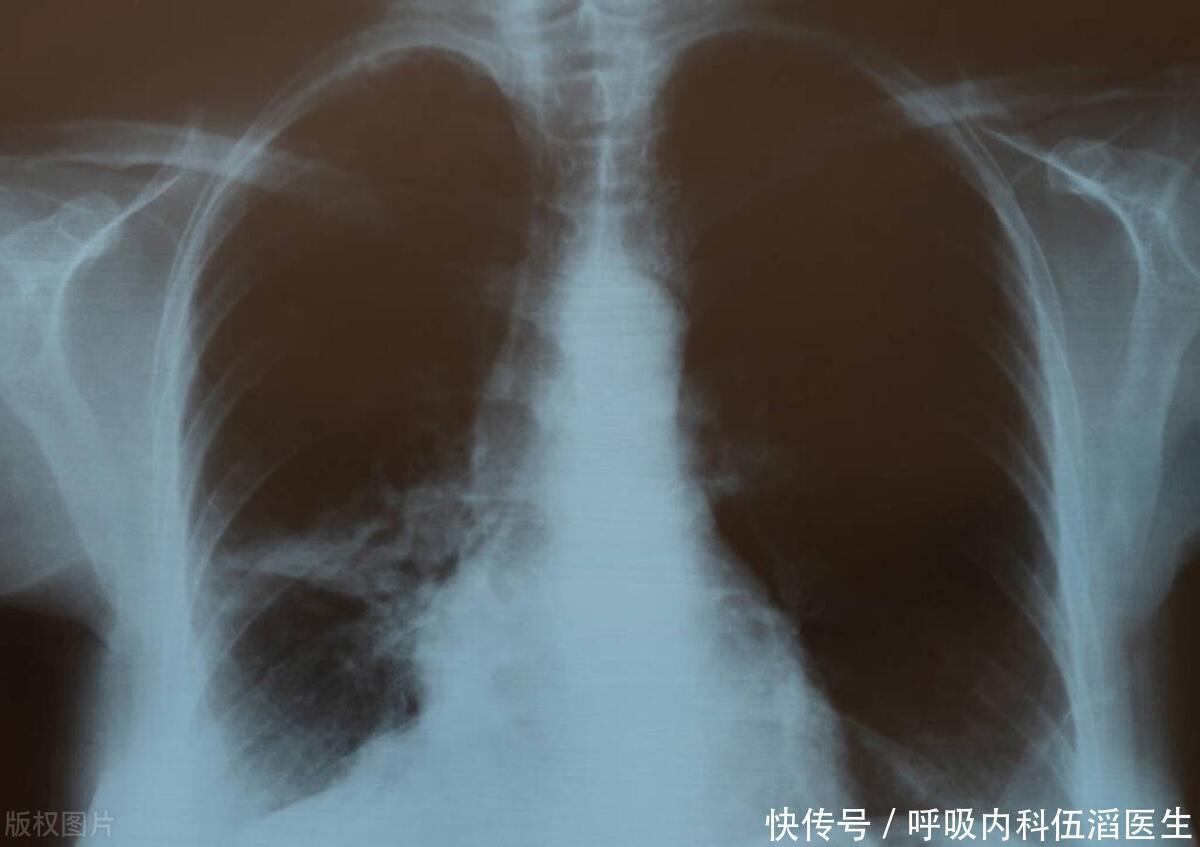

海鲜是肺结节催化剂?提醒:不想结节恶化,少碰三种食物

肺结节

肺部

肺癌

吸烟